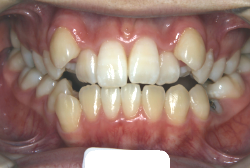

開咬

開咬という症状は、一部の歯が上下的に接触できない症状を持っています。一番よく見られるのは、奥歯は咬めるけれども前歯の部分が咬めない(閉じても前歯同士が当たらないという状態)という症状で、この状態を、前歯部開咬といいます。そのほかに、臼歯部開咬や側方開咬などいろいろ珍しい症状はありますが、通常”開咬”というと”前歯部開咬”のことをいいます。

「前歯が重ならない」という主訴で来院したケースです。診断の結果、「重症の開咬」と判明しました。

この方の場合は、マルチブラケット装置は、歯の位置づけを3次元的に正確に行うことの出来る最善の矯正方法です。したがって開咬の治療も、形の改善としては問題なく行うことが出来ます。しかし、開咬が他の症状と少し違う点は、舌や唇の動かし方に問題があることから生じた症状なので、この問題を放置したまま形だけを作っても、時間が経つと簡単に後戻りしてしまうという問題です。つまり、マルチブラケット法で形態の矯正をするのと同時に、原因となっている筋肉の動きを正常に修正しなければなりません。この筋肉の動きを正常に修正する治療が、"筋機能訓練療法(Myo-functional therapy:略してMFT)"といわれるものです。

筋機能訓練療法は、筋機能訓練療法士という特別なトレーニングを積んだ歯科衛生士が行います。内容的には、いろいろなメニューがあり、簡単なものから始めて少しずつ筋肉の力を強めていき最終的には、無意識に起きる舌の突出をなくし、正しい摂食嚥下運動を獲得するまでトレーニングしていきます。この症例は、もちろん筋機能訓練にもしっかり取り組みました。治療後は開咬が改善しただけでなく、出っ歯の症状もなくなり唇の審美性が大幅に改善しました。もちろん奥歯の噛み合わせも正しい状態が確立しています。